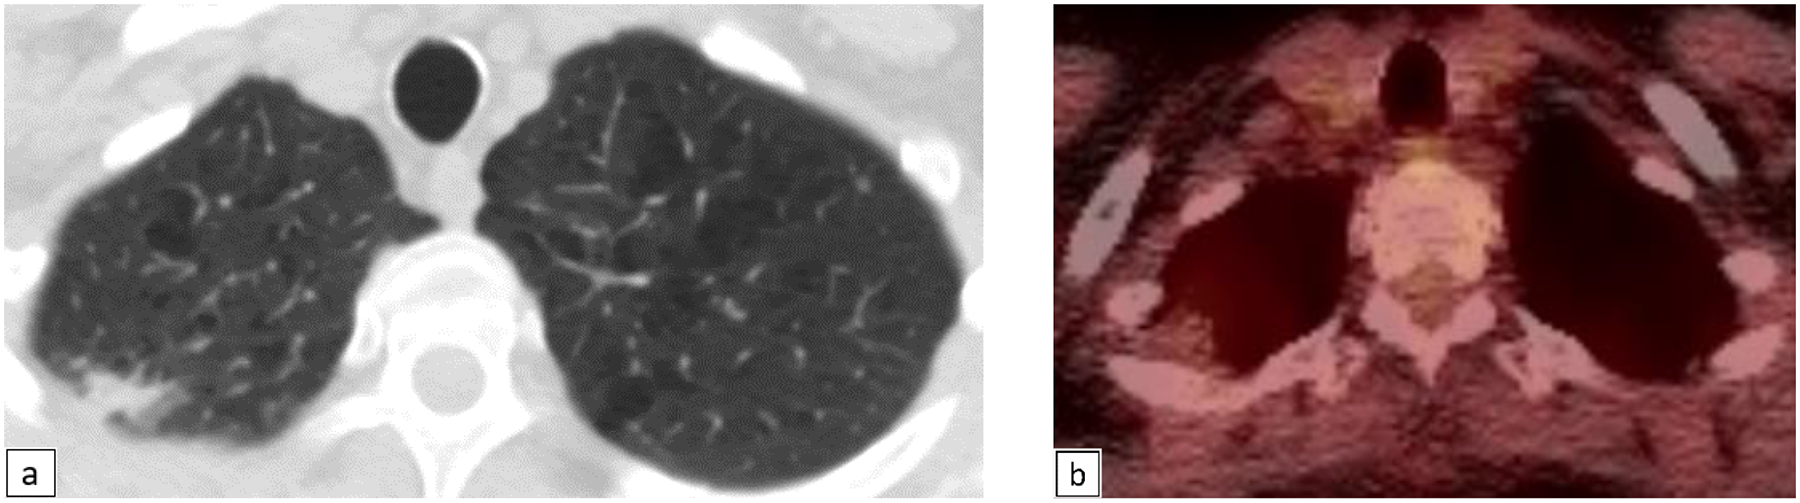

Figure 2.

65 year old female with new left upper lobe nodules (Fig 2a) (Lung-RADS category 4X). These were mildly FDG-avid on PET/CT (Fig 2b). Pathology reveals necrotizing granulomas containing numerous hyphae of uniform width, with septations and acute angle branching, consistent with aspergillus or another hyaline mold.